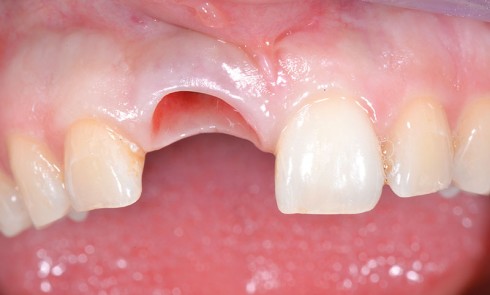

Article réservé à nos abonnés Une hyperplasie gingivale péri-implantaire

1. Quel(s) diagnostic(s) évoquez-vous ?a) Carcinome épidermoïdeb) Hyperplasie endothéliale intravasculairec) Epulis inflammatoired) Granulome pyogénique 2. Quelle est la conduite à tenir...